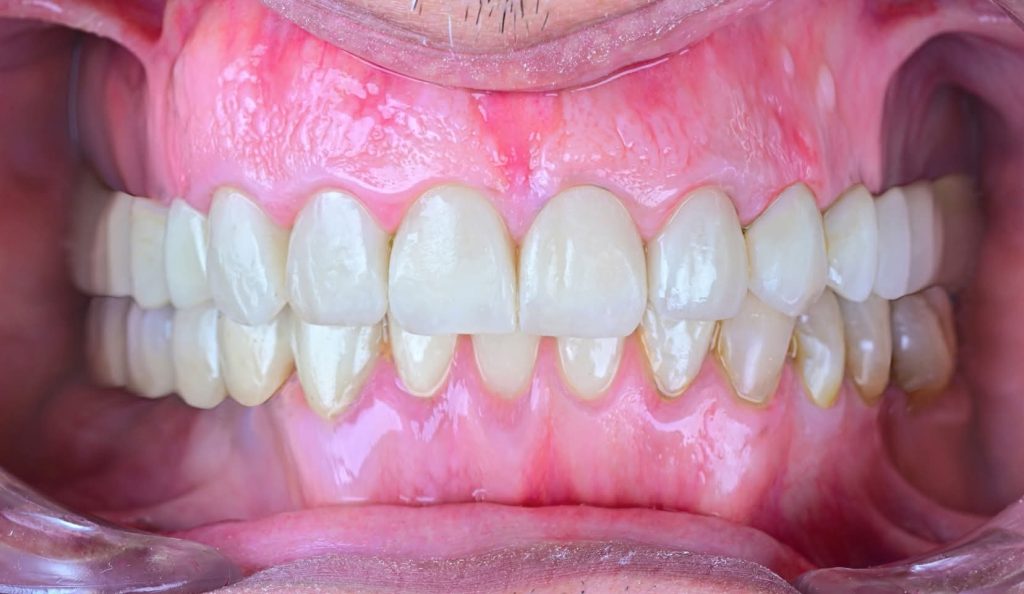

After almost 4 Years Follow-Up.

I am revisiting this Full Mouth Rehabilitation case, which was my first published case in this group.

The patient has now been under follow-up for nearly 4 years and remains very happy and comfortable.